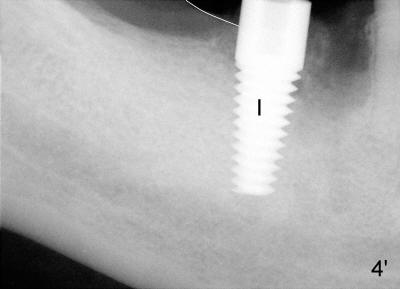

In case that there is an oral infection, submerged implant (Fig.4: I; Bicon 5x8; white line indicates gingival margin) may reduce the chance of pathogen contamination postoperatively. Fig.5 shows slight wound gaping after suture removal, one week postoperatively. In contrast, the implant in Fig.4' (Tatum 6x17) is non-submerged (white line indicates gingival margin). Two week post-operatively, an infection develops buccal to the implant (Fig.5'). Bone loses around the non-submerged implant 1 month after placement (Fig.4"). Finally the implant has to be removed. Return How to Avoid Post-implant Infection